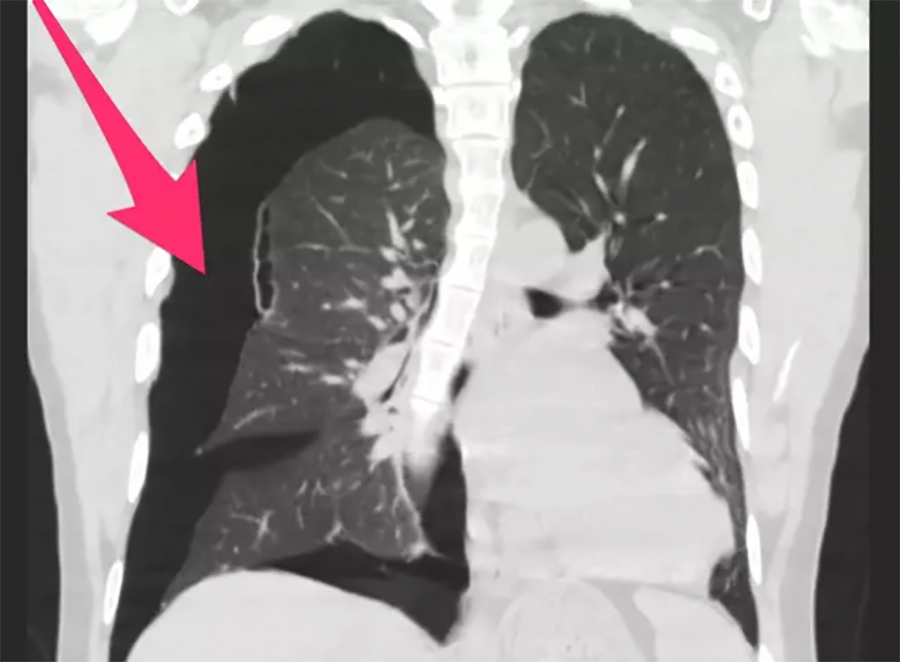

Что показывает флюорография: видимые изменения в легких

Сама по себе флюорография не может "показать" факт курения кальяна как таковой. Она не покажет никотин, смолы или частицы дыма, осевшие в легких. Основная задача флюорографии – выявить структурные изменения в легочной ткани и органах грудной клетки, которые могут свидетельствовать о наличии заболеваний.

Однако, если курение кальяна уже привело к развитию патологических изменений, флюорография вполне способна их обнаружить. К таким изменениям относятся:

- Утолщение стенок бронхов: При хроническом бронхите, вызванном раздражением дыхательных путей, стенки бронхов могут утолщаться, что видно на снимке.

- Уплотнение легочной ткани: Это может быть признаком воспалительных процессов, фиброза или других патологий, развившихся из-за длительного воздействия вредных веществ.

- Изменение легочного рисунка: Легочный рисунок становится более выраженным или деформированным, что указывает на хронические изменения в бронхах и сосудах легких.

- Очаговые тени и инфильтраты: Могут свидетельствовать о наличии воспалительных процессов, туберкулеза или даже опухолей.

- Эмфизема легких: В некоторых случаях длительное курение может привести к разрушению легочных альвеол и образованию воздушных полостей, что также может быть заметно.

Таким образом, если курение кальяна уже оказало существенное негативное влияние на ваши легкие, флюорография, скорее всего, покажет эти изменения. Важно понимать, что флюорография – это скрининговый метод, который позволяет выявить подозрения на патологию. При обнаружении любых изменений, врач назначит дополнительные исследования, такие как КТ легких, бронхоскопия или лабораторные анализы, чтобы уточнить диагноз.